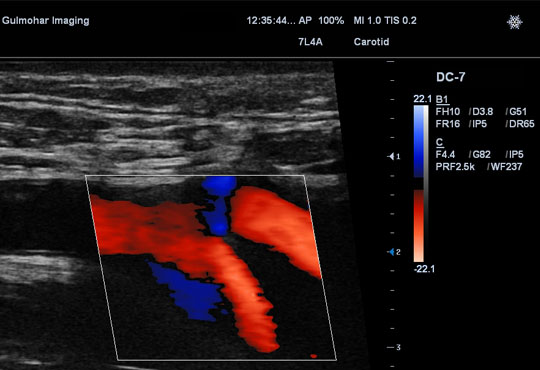

Performed through specialised transducer to evaluate carotid Arterial System (Arteries that supply brain, face and neck). To confirm or rule out blocks, if any and atherosclerotic changes.

It's a meticulous and lengthy procedure that requires optimal focus and patients cooperation. It is performed through high resolution transducer (probe) and can diagnose atherosclerotic changes and / or partial to complete blocks in arteries, if any.